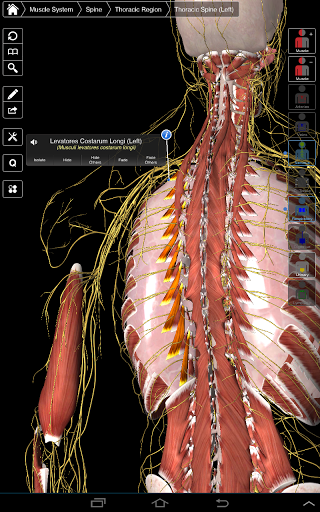

Essential Anatomy 3 representa lo último en tecnología 3D innovadora y diseño innovador. Un motor de gráficos 3D de vanguardia, creado a medida por 3D4Medical desde cero, alimenta un modelo anatómico altamente detallado y ofrece gráficos de calidad excepcional que ningún otro competidor puede lograr.

La aplicación representa un enfoque único para el aprendizaje de la anatomía general. Los gráficos no tienen paralelo y hacen que el aprendizaje, a través del uso de contenido informativo y características innovadoras, sea una experiencia rica e interesante.

⁃Músculos

NUEVA TECNOLOGÍA 3D

Essential Anatomy 3 es receptivo, visualmente impactante y sin esfuerzo. La aplicación es totalmente en 3D, lo que significa que puedes ver cualquier estructura anatómica de forma aislada y desde cualquier ángulo.

La funcionalidad inteligente que se encuentra dentro de la aplicación permite al usuario eliminar capas de músculo a través de la herramienta 'bisturí'. Esta aplicación ofrece a los usuarios la posibilidad de activar / desactivar sistemas sin la necesidad de anular la selección de estructuras individuales o mezclarse en una multitud de pestañas regionales predefinidas, como otras aplicaciones.

---- Más de 4,000 estructuras anatómicas altamente detalladas

---- Nomenclatura latina para cada estructura anatómica